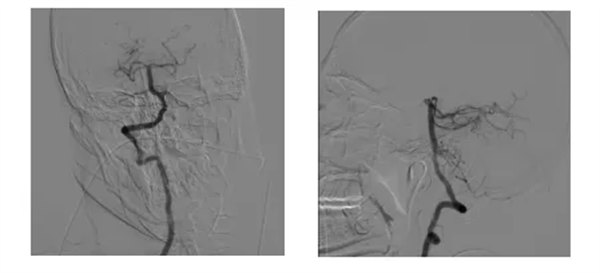

入院后神經(jīng)內(nèi)三科為患者問(wèn)診、查體完善相關(guān)檢查。患者嗜睡,言語(yǔ)含糊,雙眼垂直注視麻痹,右側(cè)鼻唇溝變淺,咽反射減弱,懸雍垂偏右,雙側(cè)Babingski征陽(yáng)性,腦膜刺激征陰性。NIHSS評(píng)分 6分 ,GCS評(píng)分11分,發(fā)病前MRS評(píng)分0分,發(fā)病后MRS評(píng)分5分。考慮急性腦梗死,查體過(guò)程中患者病情波動(dòng)性進(jìn)展加重意識(shí)呈嗜睡——清醒——昏睡,出現(xiàn)間斷呼吸暫停,雙側(cè)瞳孔縮小,光反消失,雙肺呼吸音低。神經(jīng)內(nèi)三科席聰、馮曉偉卒中團(tuán)隊(duì)分析,結(jié)合患者病史、體征及相關(guān)檢查,考慮為后循環(huán)急性腦梗死,患者醒后卒中,發(fā)病時(shí)間不祥,靜脈溶栓存在禁忌,席聰主任團(tuán)隊(duì)針對(duì)患者的病情,與家屬溝通后憑借精湛的醫(yī)術(shù)和豐富的經(jīng)驗(yàn),為患者實(shí)施了全腦血管造影術(shù),造影顯示:右側(cè)大腦后動(dòng)脈P1段中度狹窄,狹窄率55%,右側(cè)大腦后動(dòng)脈P2段中度狹窄,狹窄率50%,右側(cè)椎動(dòng)脈V4段未見(jiàn)PICA顯影,席聰主任分析右側(cè)PICA雖未顯影,但患者癥狀與PICA閉塞癥狀不符合,結(jié)合右側(cè)大腦后動(dòng)脈P1段狹窄,斑塊位于管壁上側(cè),考慮II型Percheron動(dòng)脈血栓形成可能。沿右側(cè)椎動(dòng)脈導(dǎo)管推注替羅非,術(shù)后病人完全清醒,應(yīng)答準(zhǔn)確,GCS升至15分,NIHSS評(píng)分降至2分班6ml行動(dòng)脈溶栓,溶栓后右側(cè)椎動(dòng)脈血流明顯加快,V4段管壁較前光滑,順利完成手術(shù),手術(shù)效果立竿見(jiàn)影,患者轉(zhuǎn)危為安,送入病房進(jìn)行后續(xù)治療。